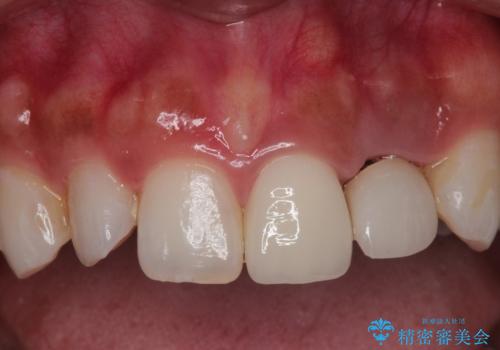

- 左上の前歯が外れそうとのことで来院されました。

レントゲンを撮影すると、不適合のかぶせ物が装着されており、根管治療も不十分でした。

左上の1番目、2番目の歯を根管治療からの再治療を行う計画としました。